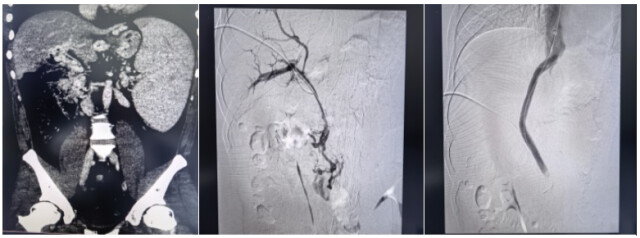

湖南日报4月1日讯(全媒体记者 周阳乐 通讯员 何倚 马小倩 颜智敏 袁恺悦)近日,中南大学湘雅三医院放射介入团队成功完成一例国内罕见的超高难度经颈静脉肝内门体分流术(TIPS)。该手术突破介入诊疗临床极限,为一名被致命出血风险困扰7年的患者重新打通血管通道,实现了在复杂门静脉高压、疑难血管疾病介入诊疗领域的重要突破。

“没有通道,我们就为生命开辟一条通道。”面对患者与家属的殷切期盼,湘雅三医院放射介入团队副主任(主持工作)梁琪带领团队迎难而上。术前,团队反复研读影像学资料,全面评估血管条件与手术风险,制定了周密的个体化手术方案。术中,团队凭借深厚的介入诊疗功底,沉着操控、精准穿刺,在闭塞多年的血管中耐心探查、精细开通,最终成功放置支架、搭建起肝内分流“生命桥”,显著降低门静脉压力,从根源上解除致命大出血风险,实现微创、安全、高效救治。